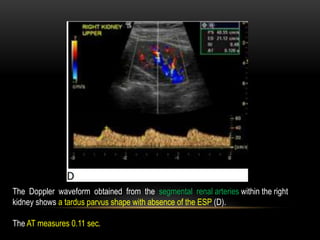

The Doppler waveform obtained from the segmental renal arteries within the right

kidney shows a tardus parvus shape with absence of the ESP (D).

The AT measures 0.11 sec.